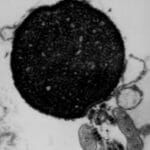

Electron Micrograph

Electron Micrograph

Electron Micrograph